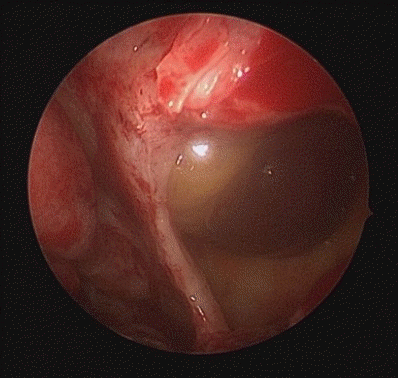

A 19-year-old male presented to the Emergency Department of Chonnam National University Hospital after sustaining facial trauma from slipping on the stairs. Severe swelling involving the left periorbital region and an approximately 2.0 cm laceration wound were observed on the left lower lip. The patient’s vital signs were stable, and neurological function was intact.Clinical examination revealed normal ocular motility, intact infraorbital sensation, and well-maintained globe position without diplopia or enophthalmos.A maxillofacial CT scan was performed for further evaluation. CT imaging demonstrated fractures of the left medial orbital wall, inferior orbital wall, and nasal bone (Fig. 1). The medial wall defect was located adjacent to the ethmoid sinus with partial herniation of orbital soft tissue. The inferior orbital wall fracture extended posteriorly with minimal displacement of the bony fragments, and a depressed nasal bone fracture was also confirmed.Initial management included primary closure of the lower-lip laceration under local anesthesia. Reduction of the orbital and nasal bone fractures was performed under general anesthesia using a multidisciplinary approach involving the Departments of Otorhinolaryngology and Oral and Maxillofacial Surgery.First, the medial orbital wall was repaired by the otorhinolaryngology team using an endoscopic transnasal approach with a navigation system (Fiagon Navigation System, Fiagon GmbH, Hennigsdorf, Germany). After uncinectomy and anterior ethmoidectomy, additional posterior ethmoidectomy was performed, followed by widening of the frontal and sphenoid ostia. This provided a clear surgical field for orbital compression and visualization of the left medial orbital wall fracture site (Fig. 2). The medial wall showed diffuse destruction with generalized herniation of the periorbita. After careful reduction of the herniated contents, a customized silastic sheet was inserted in an inverted U-shape (Fig. 3).Subsequently, the oral and maxillofacial surgery team performed intraoral access for reconstruction of the orbital floor. A vestibular incision approximately 3 cm in length was made, extending from the left canine to the first molar region. A bony window measuring approximately 15 × 10 mm was created in the anterior wall of the maxillary sinus to provide direct visualization of the inferior orbital wall defect. Herniated orbital tissue was carefully repositioned into the orbital cavity, and the orbital floor was anatomically reconstructed. A titanium miniplate with screws (DePuy Synthes, Oberdorf, Switzerland) was applied across the fracture line to achieve rigid fixation (Fig. 4). Layered closure was then performed to ensure proper wound healing and anatomical restoration.Finally, closed reduction of the nasal bone fracture was performed to restore nasal contour and symmetry. To maintain medial wall reduction and provide uniform compression, Merocel® (Medtronic Xomed, Jacksonville, FL, USA) was inserted into the ethmoid cavity. The operation proceeded smoothly without intraoperative bleeding, orbital content injury, or infraorbital nerve disturbance, indicating stable surgical control.Immediate postoperative CT confirmed successful reduction of both fractures. The patient experienced complete resolution of diplopia and ocular discomfort, while infraorbital sensation remained mildly decreased but improving. At two weeks, Merocel® packing was removed, and routine dressing was performed. At two months, follow-up CT and endoscopic examination demonstrated stable reconstruction, and the silastic sheet was removed (Figs. 5 and 6). The patient’s sensation had nearly recovered, and postoperative outcomes remained stable with preserved ocular movement, normal globe position, and proper occlusion.

Figure 2.

Endoscopic medial wall exposure Endoscopic view showing herniated periorbita at the medial wall defect.